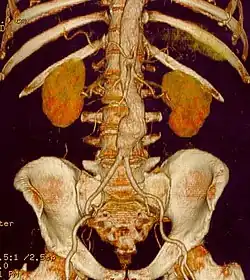

| CT reconstruction image of an abdominal aortic aneurysm | |

- Computed tomography (CT) and magnetic resonance angiogram (MRA) - These imaging techniques give a more detailed view of the aneurysm. These techniques may be used to gather information about aneurysm's relation to the blood vessels of the kidney or other organs. This information may be useful before surgery. CT is used to watch the growth of a thoracic aortic aneurysm.